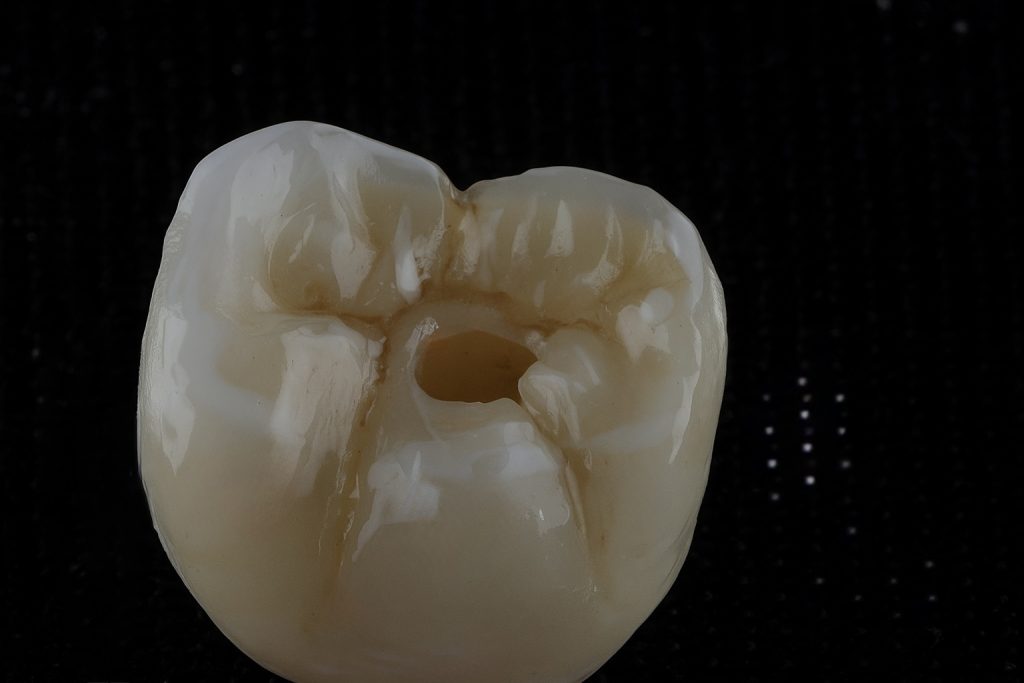

3. Crown Fabrication

A monolithic zirconia prosthesis was fabricated with precise occlusal morphology and central screw access for retrievability. The restoration was individually characterised and glazed to reproduce enamel texture and hue harmony with adjacent teeth.

5️⃣ Screw-retained zirconia restoration – occlusal view